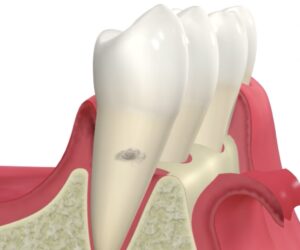

治療のイメージはこんな感じです。

深い歯周ポケットの奥のほうに歯石がついているので、

まずはその歯石を見える状態にする必要があります。

歯ぐきに切開を入れ、めくって歯の根元を目視で確認します。

もちろん麻酔をしているので痛くはありません。

その状態で歯石を取り、歯根をツルツルにします。